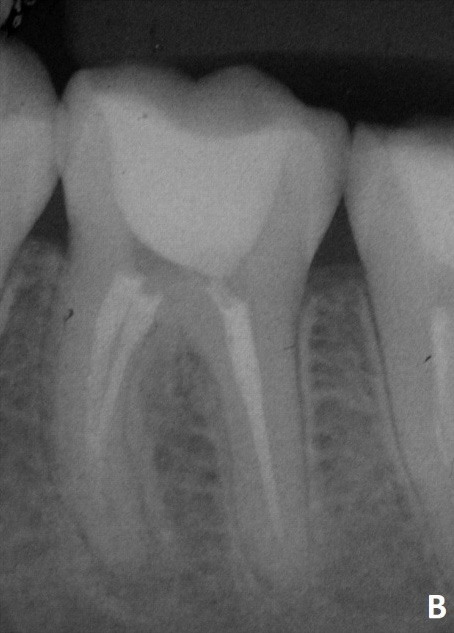

Radiographic (B) aspects of tooth 36.